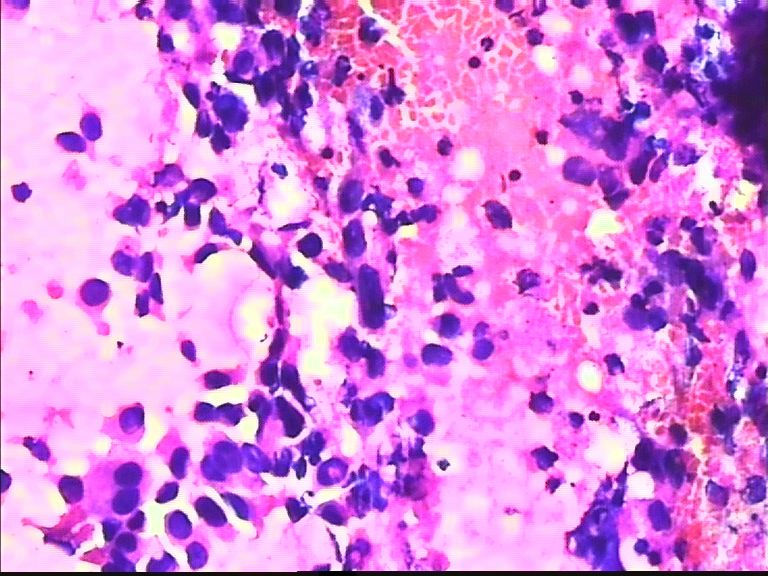

38岁 乳腺肿瘤 女

恶性肿瘤细胞

导管癌

乳腺导管癌

我试着说一下,不对的地方请其他老师修正。良恶性细胞鉴别主要还是观察细胞核的形态和大小、染色质颗粒是否细腻均匀,核膜是否光滑增厚等,还有涂片的背景是否有坏死等。这个病例就是一个很明显的恶性病例。形态学的东西讲究的就是多看多比较,慢慢就能掌握的。不急哦!

非常明显的恶性肿瘤细胞,倾向浸润性导管癌。细胞异型性大,非常弥散,未见肌上皮细胞。

润性导管癌,细胞大小不一、异形明显、粘附性差,尤其是在同一堆细胞内。